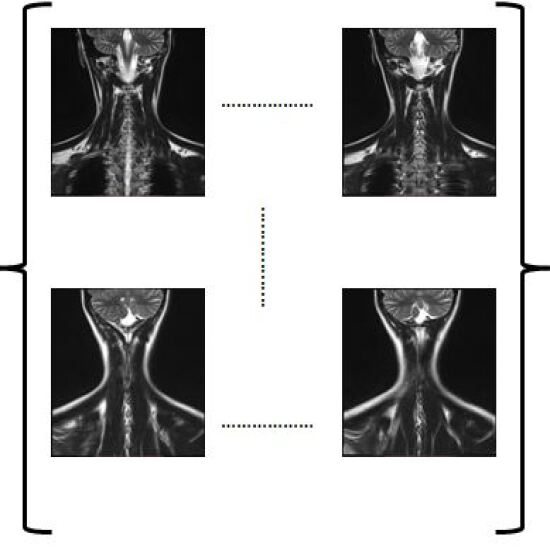

Figure 2: Splitting a 2D image slice for a human spine

Initially, the 2D2𝐷2D slices are split in 4 sub parts as shown in Figure 2 for a human spine, and the data set in divided in two parts. We use single instruction multiple data architecture using 8 logical cores. In parallel, for each block of sub-image, a 3D3𝐷3D matrix is created which is filled with the corresponding data leaving the specified slice gap in between slices as specified for each set as shown in Figure 3. Then edge preserved kriging interpolation is used to generate the 3d subimages. If we want to visualize these sub-images, then we can apply marching cube with color map and visualize the images as shown in Figure 4 and the complete 3D image for visualisation of full spine is as in Figure 5.